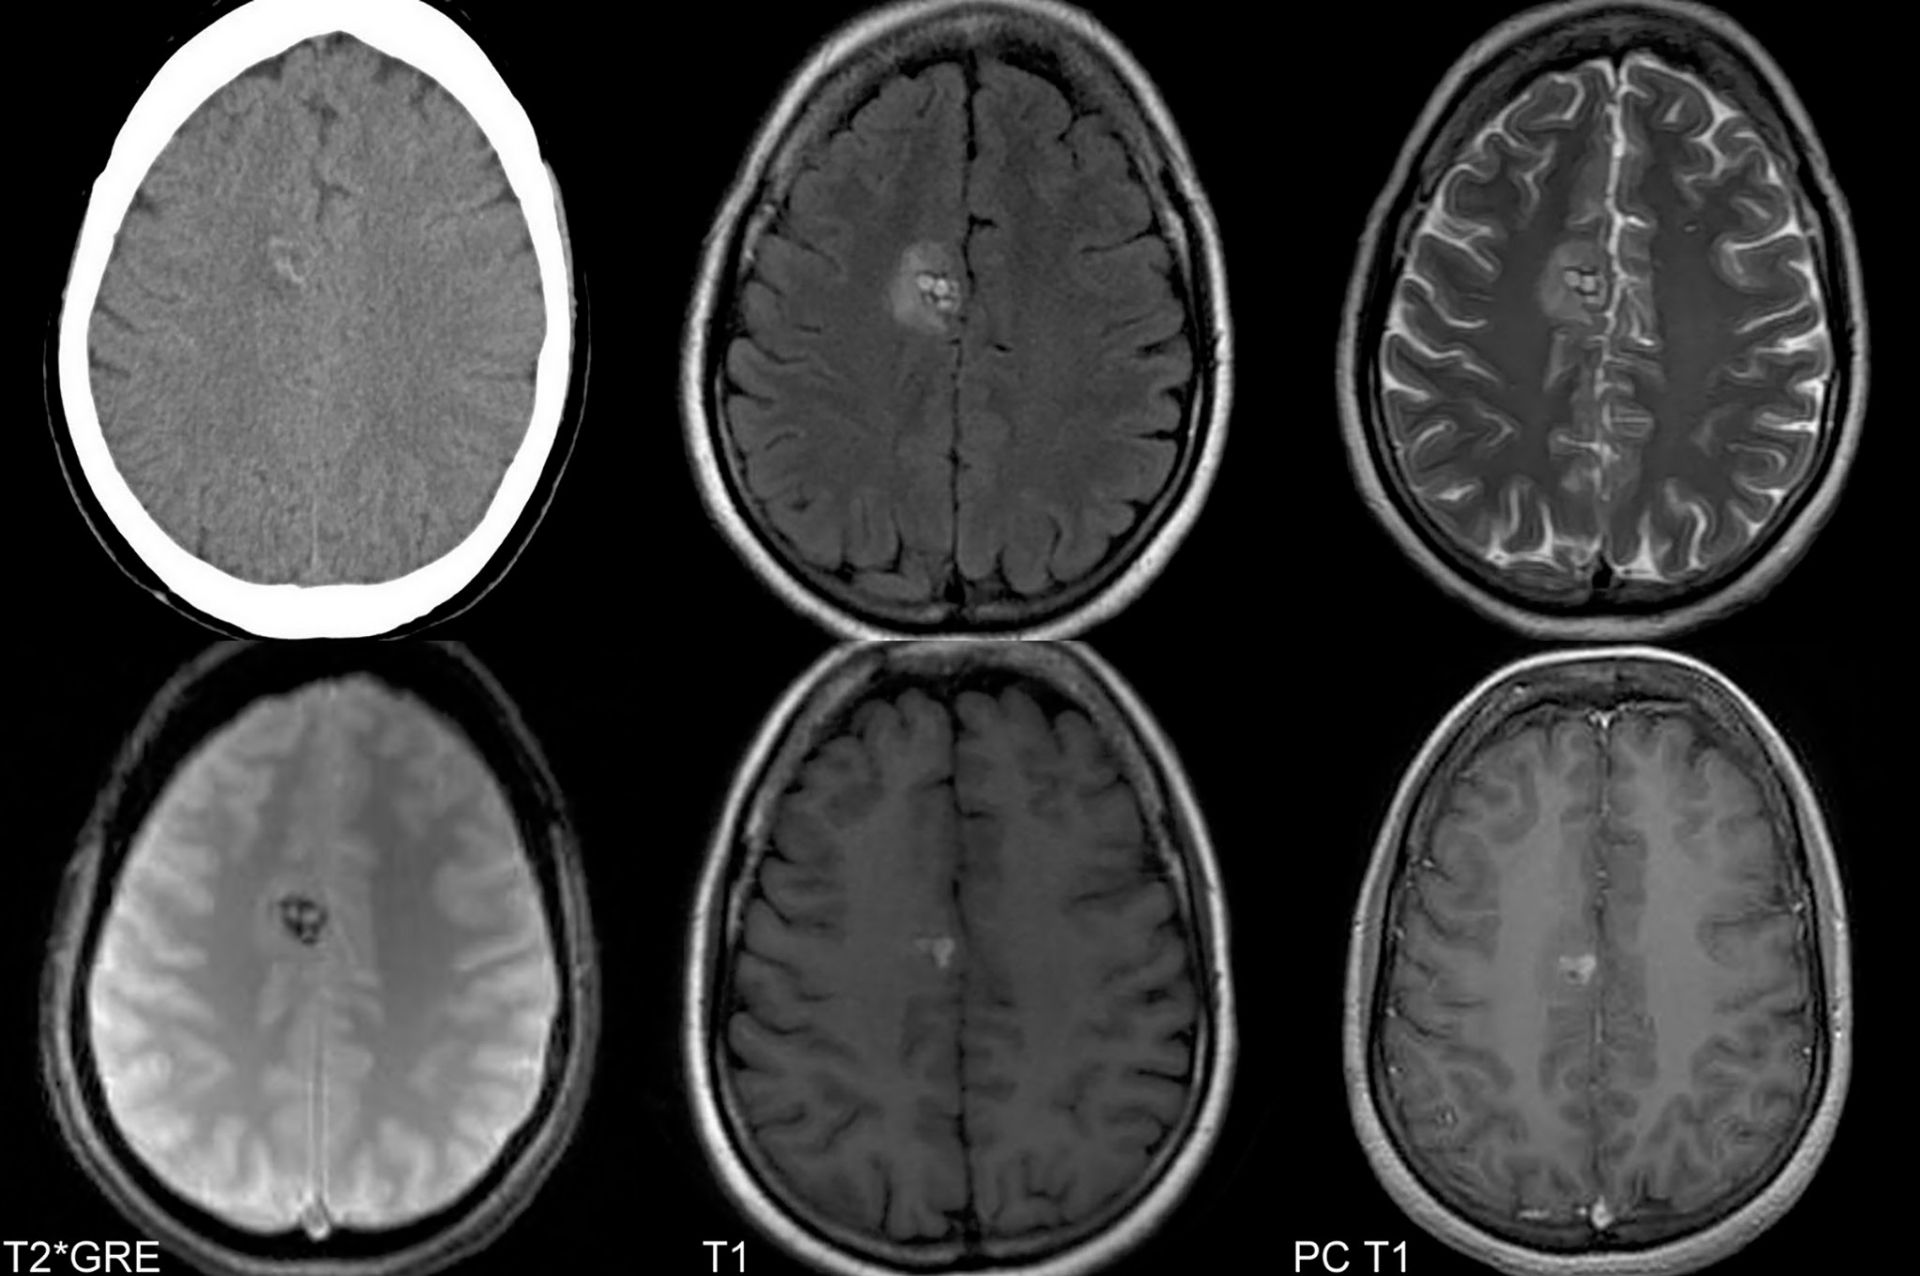

Cavernoamele cerebrale sunt leziuni benigne dinamice, cu o leziune înconjurată de ţesut gliotic ce nu conţine în interior ţesut nervos, localizate de obicei în substanţa albă. Cavernoamele se întâlnesc în două forme: solitară (cea mai frecventă) și familială (15-20%, cu transmitere autozomal dominantă). Ca simptomatologie, cavernoamele pot fi asimptomatice (12%) sau pot cauza crize comiţiale (40-50%), deficite neurologice tranzitorii sau progresive (20%), hemoragie (10-25%), cefalee. Crizele comiţiale reprezintă simptomul iniţial, crizele fiind determinate de depozitele de hemosiderină, agent epileptogenic bine cunoscut. Specialistul poate suspiciona un angiom cavernos la un pacient tânăr (20-40 de ani) cu comiţialitate. Deoarece cavernomul este bine delimitat de ţesutul cerebral înconjurător, acesta poate fi complet excizat fără a produce deficite suplimentare. O atenţie deosebită trebuie să se acorde excizării, pentru că orice rest se poate regenera. Riscurile tratamentului intervenţional depind de mărimea și de localizarea cavernomului, de condiţia biologică a pacientului, dar și de experienţa neurochirurgului.